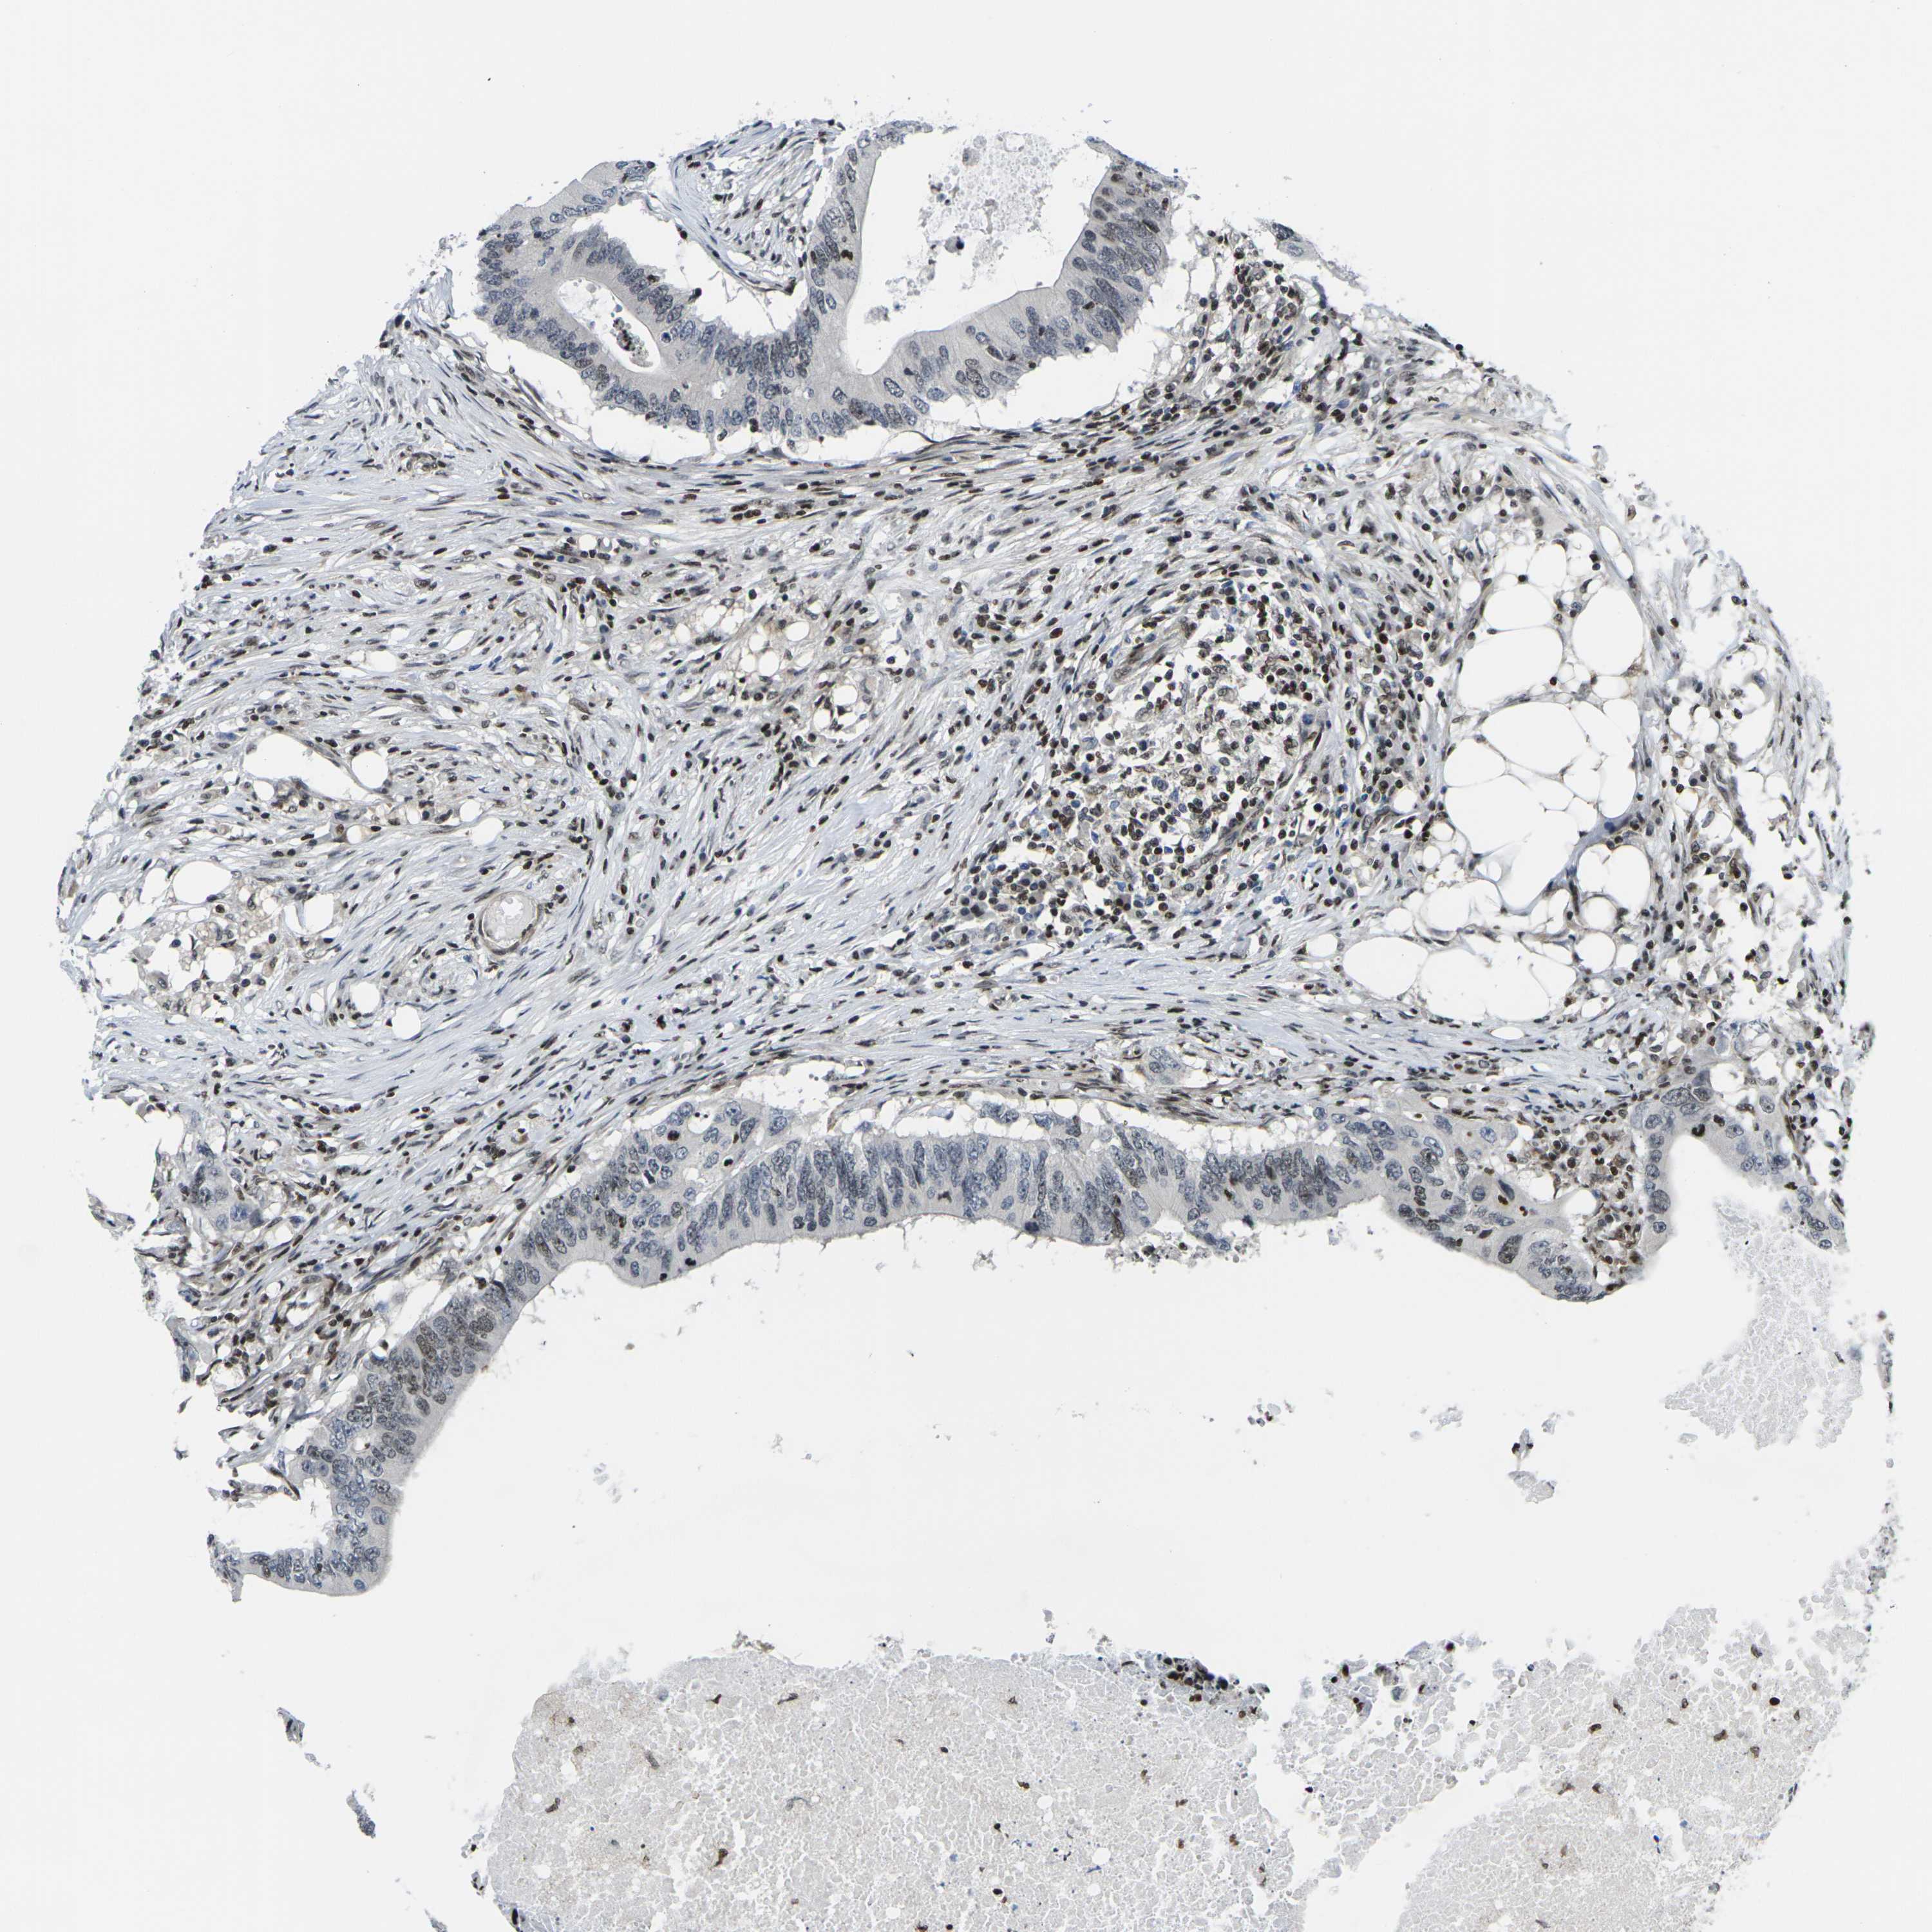

CANCER COLORECTAL CANCER Show tissue menu

Colorectal cancer

Human cancer

Colon adenocarcinoma